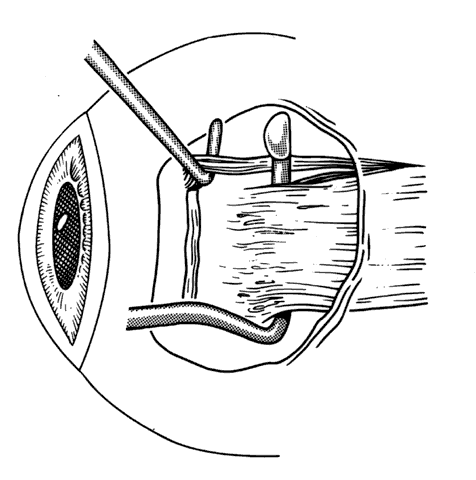

Reintervention to correct strabismus is indicated if a technical problem occurred immediately after the initial procedure. A muscle that has become disinserted or is “lost” postoperatively requires immediate exploration and correction of the problem (Figs. 2 and 3). A similar situation may occur when a previously operated muscle retracts ("slips") inside the muscle capsule (Fig. 4). The slipped muscle will appear paretic, and early surgical intervention should be considered. The clinical pictures of these technical failures are very similar. There is poor function of the affected rectus muscle, and the induced strabismus will be noncomitant. Operations may be performed on the incorrect eye muscles or eye (Fig. 5). If this occurs, reoperation should not be delayed.

Fig. 4. Failure to incorporate a portion or the entire tendon of the muscle when sutures are placed near the insertion can permit a portion or all of the muscle to slip posteriorly and produce an exaggerated recession effect. On exploration, the muscle capsule will be present but the tendon will be retracted within the muscle capsule.